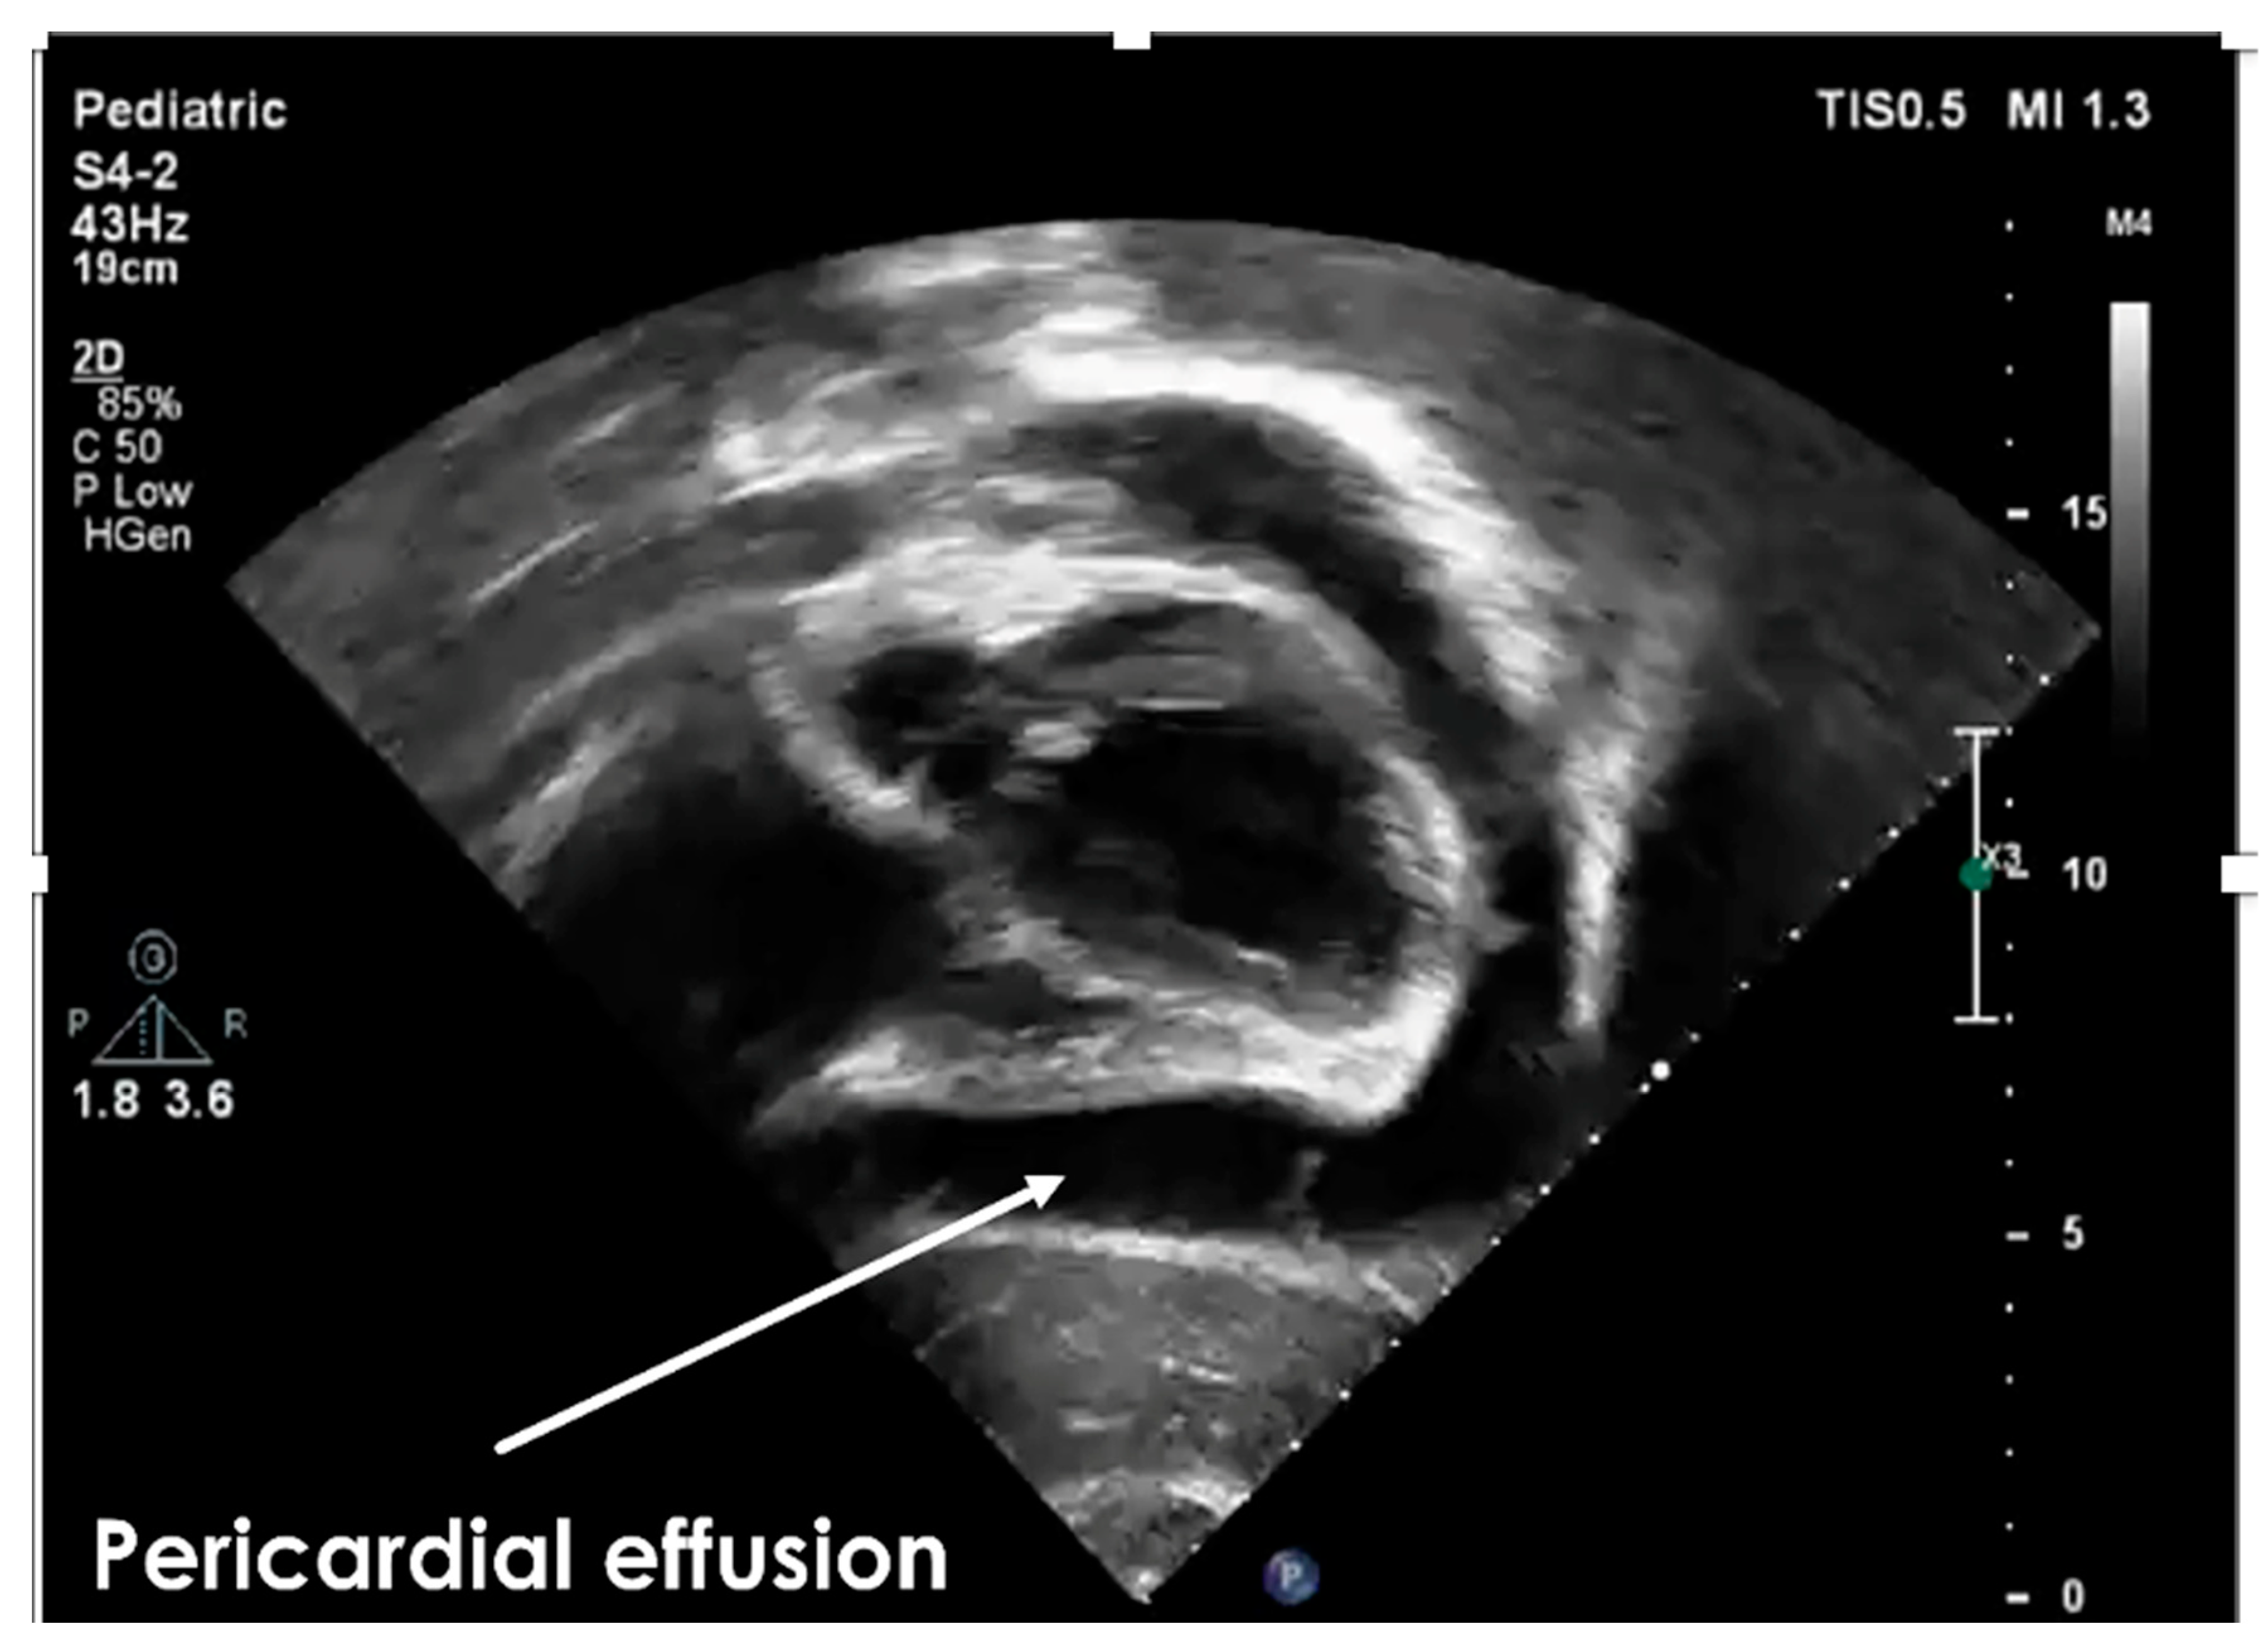

2. Case Report